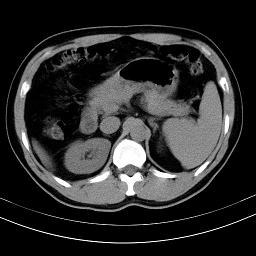

标题: CT18388:肝脏膈肌间隙内大量脂肪密度影 [打印本页]

标题: CT18388:肝脏膈肌间隙内大量脂肪密度影

腹腔脂肪沉积过多

腹腔脂肪沉积症

脂肪沉积症

激素治疗的病人容易脂肪沉积